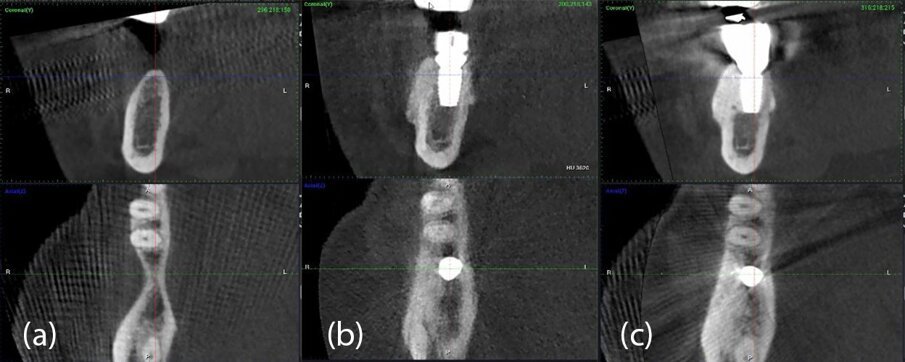

Una paziente di 51 anni di sesso femminile ha frequentato la nostra clinica cercando una riabilitazione in un sito edentulo inferiore 46. L’elemento dentale 46 è stato estratto più di 4 mesi prima della consulenza e non è stato utilizzato alcun materiale per la conservazione dell’alveolo. La paziente era una non fumatrice in buona salute, senza malattie parodontali (nessuna perdita di attacco, tasche al sondaggio e BoP). È stato eseguito un esame pre-operatorio con tomografia computerizzata a fascio conico (CBCT) nel quarto quadrante inferiore, che ha rivelato una significativa perdita ossea orizzontale nella zona edentula (Fig. 1). La densità ossea è stata classificata come tipo 2 e la distanza dal margine alveolare più coronale al canale alveolare inferiore era sufficiente per posizionare un impianto dentale (più di 10 mm) (Fig. 1). L’esame clinico ha rivelato una larghezza del tessuto cheratinizzato di più di 4 mm sulla cresta comunque sottile (Fig. 2). Il paziente è stato trattato con la tecnica del Poncho Lamina per un processo di ottimizzazione in un solo passo (Processo O.S.O.) nel sito 46. In questo caso, abbiamo selezionato e utilizzato un impianto MIS V3 (MIS Implants Technologies) e una ben documentata barriera corticale Soft Lamina 25x25 (Osteobiol by Tecnoss). L’ottimizzazione del tessuto molle è stata ottenuta con un moncone personalizzato generato tramite il sistema VPI Cervico (VP Innovato Holdings).

Fig. 1_Immagini CBCT pre-operatorie del sito 46.

Ri-valutazione radiologica

Le immagini CBCT sono state ottenute utilizzando un sistema di radiografia computerizzata CS8100 3D Carestream (Carestream Health) con una dimensione di voxel di 0,150 mm e un campo visivo di 8x9 cm prima (T1) e 16 settimane (T2) dopo l’inserimento dell’impianto. I file originali in formato DICOM sono stati importati nel software Romexis (Planmeca) per l’analisi. Per entrambi i set di dati T1 e T2, abbiamo selezionato per la valutazione delle sezioni trasversali nel mezzo del sito sulla sezione assiale e perpendicolare alla cresta alveolare (Fig. 25).